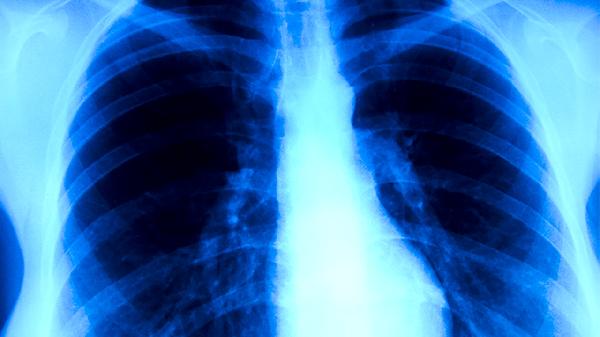

肺结核患者的用药原则主要包括早期用药、联合用药、适量用药、规律用药和全程用药。肺结核是由结核分枝杆菌引起的慢性传染病,规范用药是治疗的关键。